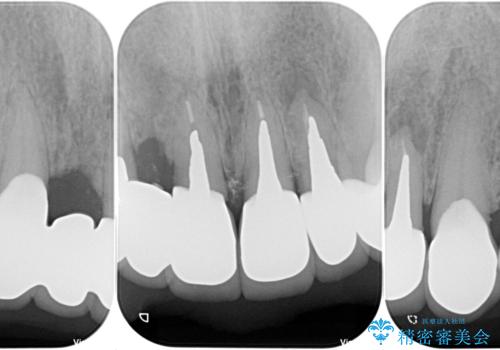

- 治療中の医院で装着した仮歯が汚れていて恥ずかしいとのことで来院された患者様です。

仮歯が不適合で歯肉が腫脹していたため、しっかりと調整した新しい仮歯にして腫れを改善した上で、オールセラミッククラウンにて補綴することとしました。

仮歯の隣の歯も詰め物の範囲が広く、仮歯をセラミックに置き換えても統一感のない口元となってしまうため、相談の結果、前歯6本をオールセラミッククラウンにて補綴治療を行うこととしました。